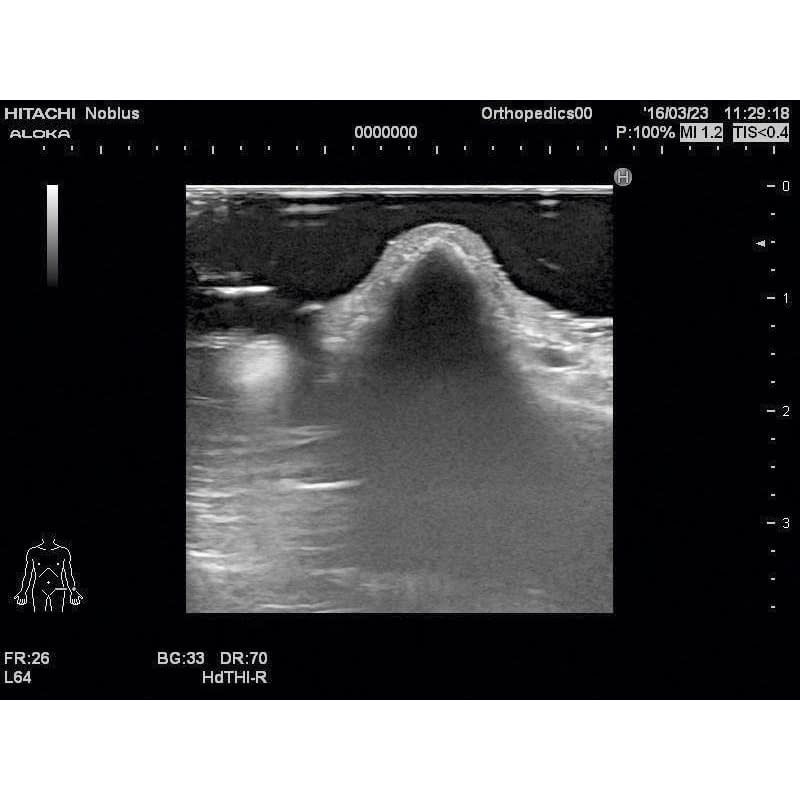

超音波診断装置(カラー)|日立製作所|超音波診断装置|ProSound α7

超音波診断装置(カラー)|日立製作所|超音波診断装置|HI VISION

超音波診断装置(カラー)|日立製作所|PRODUCT_CODE]|中古医療機器

超音波診断装置(カラー)|日立製作所|超音波診断装置|ARIETTA